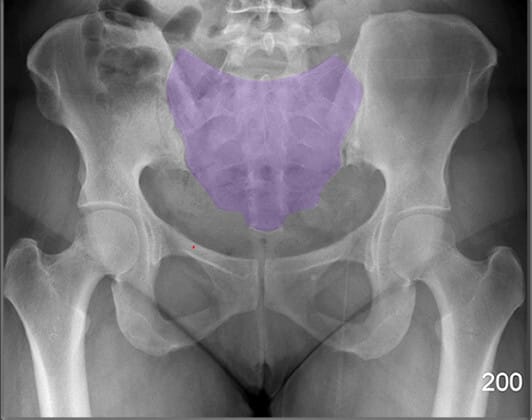

천골 (Sacrum)

| 천골 (Sacrum) |

| ✅ 요추 아래에 위치하며, 미골과 연결되는 큰 삼각형 구조입니다. AP view에서 정중앙 하부에 넓은 골 구조로 관찰됩니다. |

| 🔴 천장관절(sacroiliac joint)의 기준이 됩니다. |

미골 (Coccyx)

| 미골 (Coccyx) |

| ✅ 척추의 가장 하단에 위치한 작은 골절 구조로, 천골 아래에서 정중앙에 위치합니다. |

| 🔴 AP view에서는 짧고 좁은 골 구조로 보이며, 미골 통증(coccydynia)이나 외상 평가 시 주요하게 봐야 합니다. |

치골결합 (Pubic Symphysis)

| 치골결합 (Pubic Symphysis) |

| ✅ 치골의 정중앙에서 좌우를 연결하는 섬유연골 관절로, AP view에서 골반 중앙 하단에서 좁은 간격의 음영으로 보입니다. |

| 🔴 외상이나 분만 후 이완이나 분리(pubic diastasis)가 발생할 수 있습니다. |

상치골지 (Superior Pubic Ramus)

| 상치골지 (Superior Pubic Ramus) |

| ✅ 치골의 상단 분지로, 치골결합에서 대각선으로 위쪽으로 뻗어 장골과 연결됩니다. AP View에서는 골반 앞쪽 상부에서 연속적인 골 음영으로 나타납니다. |

| 🔴골반 고리의 안정성을 평가하는데 중요한 구조입니다. |

하치골지 (Inferior Pubic Ramus)

| 하치골지 (Inferior Pubic Ramus) |

| ✅ 치골의 하부 분지로, 좌골과 연결되어 골반 하부를 구성합니다. AP view에서 치골결합 아래쪽에서 대각선 방향으로 연장된 음영으로 나타납니다. |

| 🔴 외상성 골절이 흔히 발생하는 부위입니다. |

골반 입구 (Pelvic Inlet)

| 골반 입구 (Pelvic Inlet) |

| ✅ 천골 윗면에서 치골결합까지 이어지는 경계로, 출산 시 태아가 처음 통과하는 공간입니다. |

| 🔴 AP view에서는 전체 골반 윤곽과 함께 전후 직경을 간접적으로 추정할 수 있습니다. |

천장관절 (Sacroiliac Joint)

| 천장관절 (Sacroiliac Joint) |

| ✅ 천골과 장골 사이의 관절로, AP view상에서 좌우 대칭적으로 좁고 긴 틈으로 관찰됩니다. |

| 🔴 간격이 좁아지거나 불규칙한 경우 염증성 질환(예: 강직성 척추염)을 의심할 수 있습니다. |